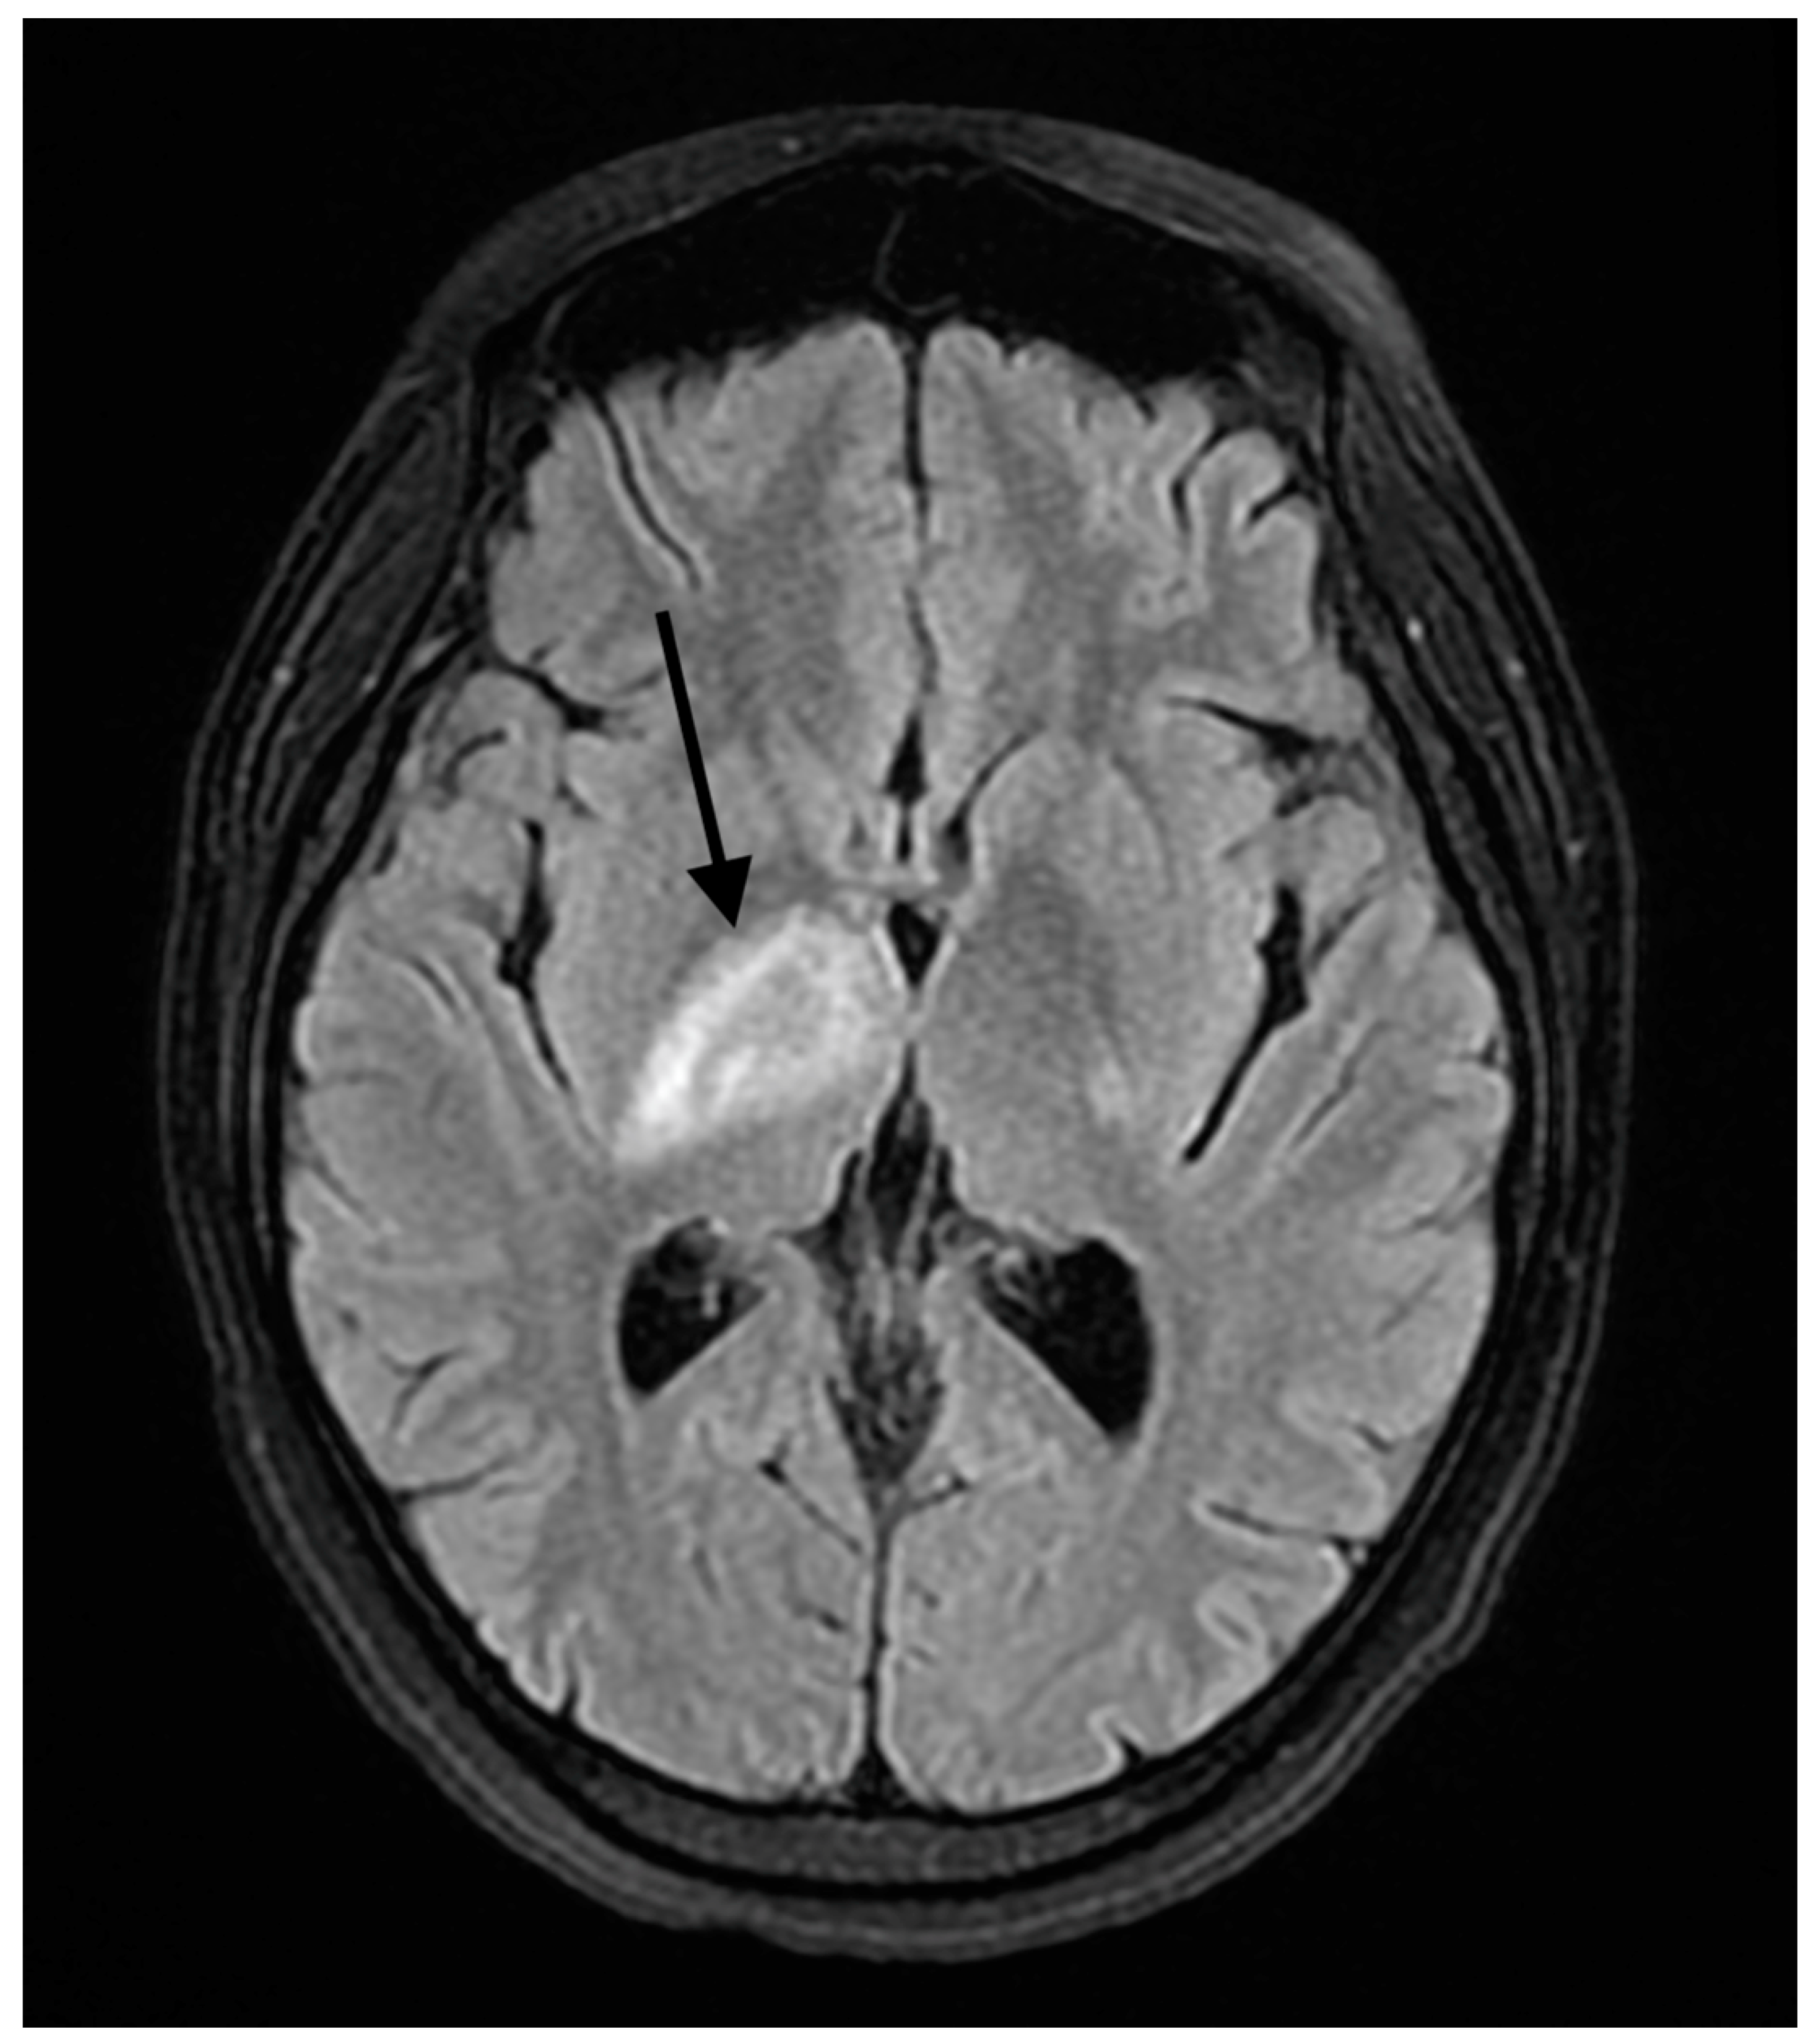

2. Detailed Case Description